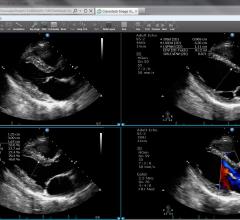

GE Healthcare, a unit of General Electric Company, developed features on the Logiq S8 general imaging ultrasound system. The innovations allow for enhanced image quality and streamlined workflow for healthcare providers, and help shorten exam times for patients. GE presented the advancements at the Radiological Society of North America (RSNA) 2013 conference.